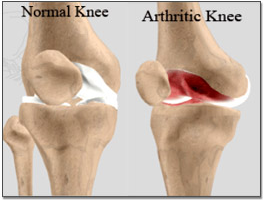

In a joint with Osteoarthritis, the cartilage breaks down and the bones rub together. The joint then loses its shape and alignment, and the bone ends thicken forming spurs (bony growths). Bits of bone or cartilage can also float in the joint space.

In a joint with Rheumatoid arthritis, inflammation and thickening of the synovial membrane occurs, causing the whole joint to look and feel swollen. The inflamed joint lining enters and damages bone and cartilage, and they are gradually digested by enzymes released from the inflammatory cells. This is caused by the immune system attacking the body’s own tissues. The joint then loses shape and alignment, and space between joints diminishes.

Symptoms can vary greatly depending on the type of arthritis and the individual. In the most common forms the symptoms are, Joints of the knees, fingers, wrists, ankles, hips, and/or elbows become stiff, swollen, tender, and painful. This pain can be greater first thing in the morning, or get worse as the day goes on. Fatigue also occurs often, and is sometimes accompanied by the inability to sleep properly. Some types of arthritis gradually spread throughout the body, while others stay concentrated in certain joints.